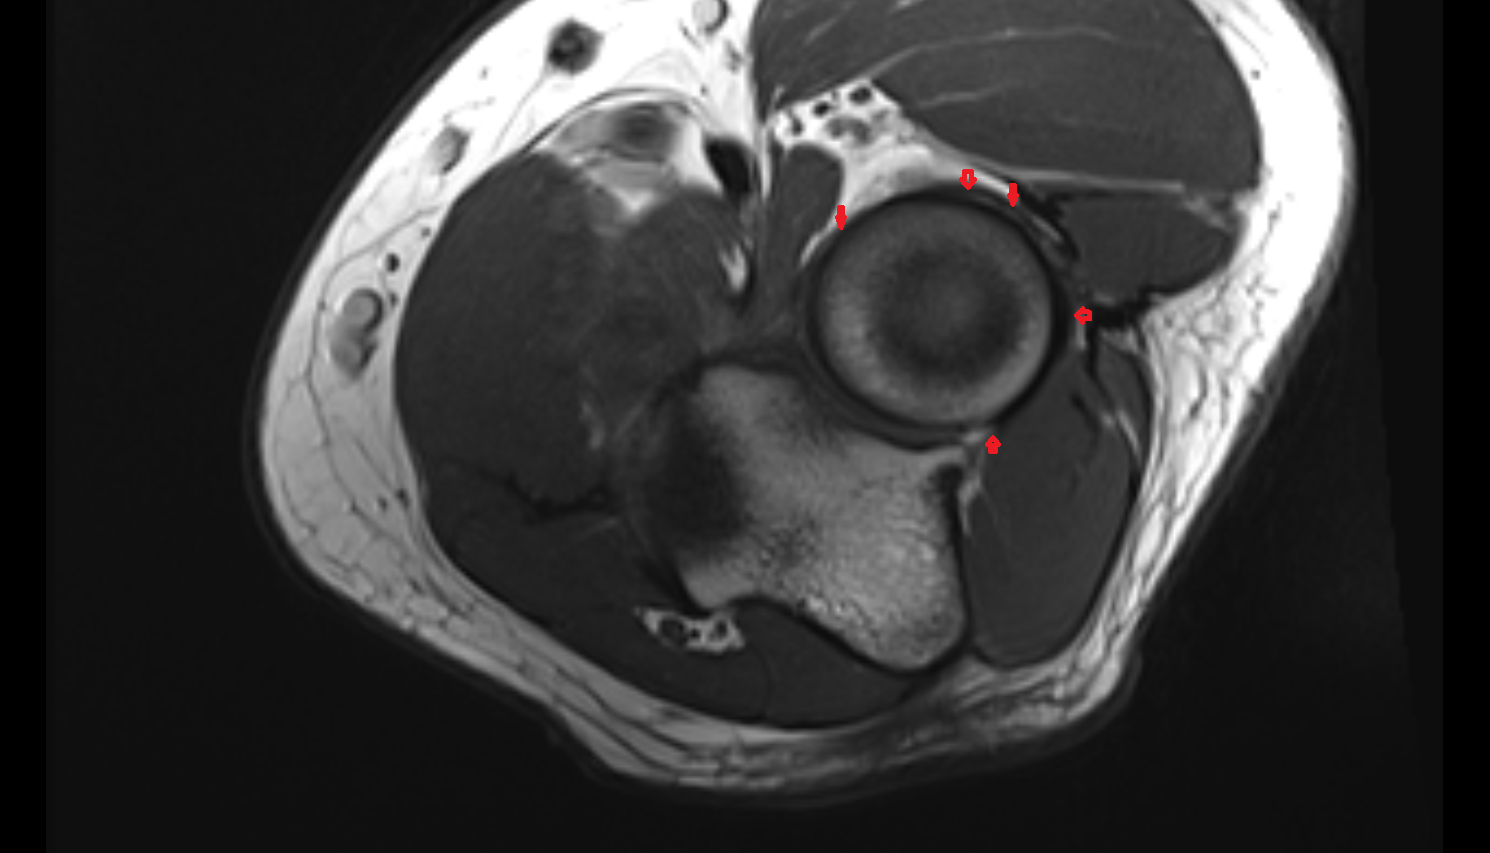

- Medial meniscus

- Lateral meniscus

- Anterior cruciate ligament

- Posterior cruciate ligament